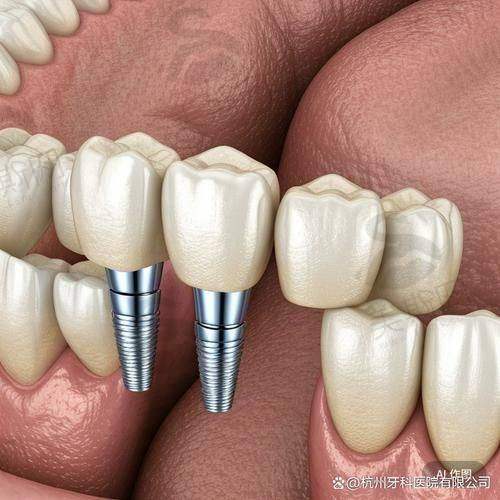

植牙技術:All - on - 4全口,香港價格(HKD):15萬 - 35萬,適合人群:牙槽骨條件中等、預算中高嘅人,特點:上下各4顆種植體,穩定性夠,恢復快

植牙技術:All - on - 6全口,香港價格(HKD):18萬 - 40萬,適合人群:想更穩定、經常食硬嘢嘅人,特點:上下各6顆種植體,承重更好,適合食牛腩、蘋果

返工黨(25 - 50歲):揀All - on - 4/6,因為手術次數少(2 - 3次),恢復快(2周可返工),唔使請長假。比如做All - on - 4,第一次植入種植體,第二次戴恒久牙冠,中間隔3個月,啱晒香港快節奏。